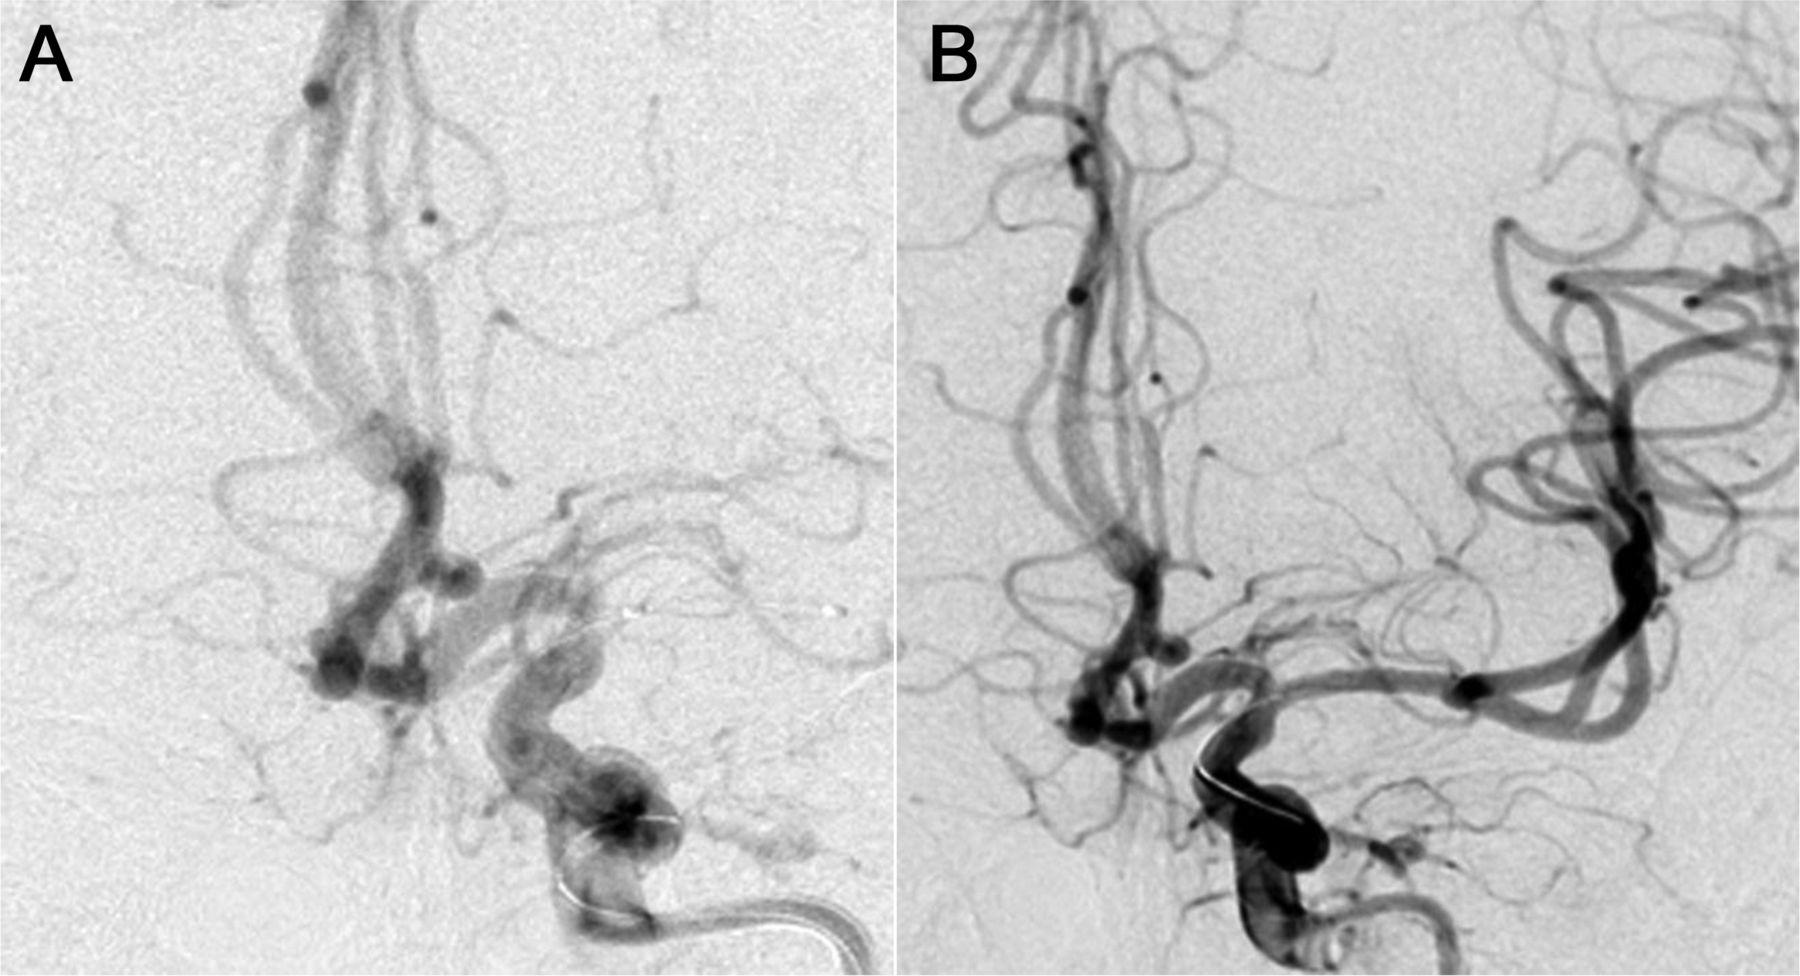

最近的报告表明,血管内治疗包括支架可以通过AIS患者超过8小时仔细选择diffusion-perfusion-based协议的基础上。14,19这些都是基于报告,可挽回的半影持续通过担保支持。据血管再通率在90%和100%之间变化,高于大多数机械或化学方法。20.,21有利的结果(分数夫人< 3)观察在3个月的50%到66%,postprocedure颅内出血/蛛网膜下腔出血率为10%到25%。20.,21病变治疗可能有一个潜在的动脉粥样硬化病灶,支架在稳定了内皮和提供快速和持续的血管再通。因此,看来支架可以做8小时之外与可靠的安全性和有效性在一个精心挑选的患者群体(图1和2)。

在见到NIH卒中量表分数是12。在远端基动脉血管摄影显示细流流,闭塞远端椎动脉(A),血管再生是通过使用3.5×12毫米多链路愿景和poststenting在脑梗死溶栓流恢复到三年级(B)。改良Rankin规模在3个月的分数是0。